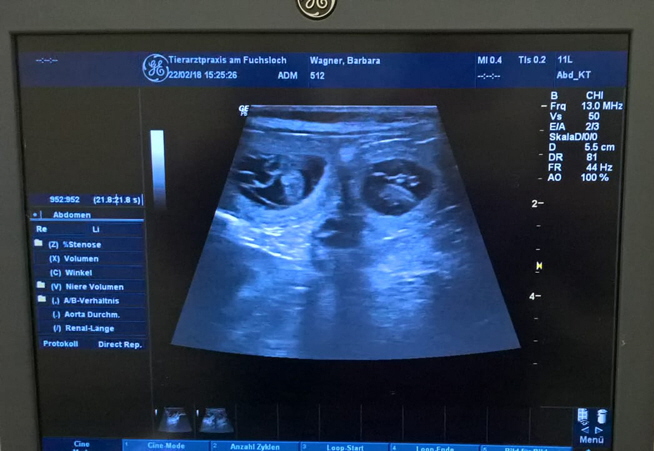

Unser Mädel ist schwanger !!!

Heute waren Vicky und Ich bei unserem Tierarzt zum Ultraschall

was ich bereits schon ahnte ist jetzt Gewissheit wir konnten auf jeden Fall schon mal 4 kleine Welpen erkennen

So und jetzt hoffen wir das alles gut läuft und wir gesunde, schöne Zwergschnauzer Welpen

von diesen beiden tollen Eltern Ende März / Anfang April bekommen